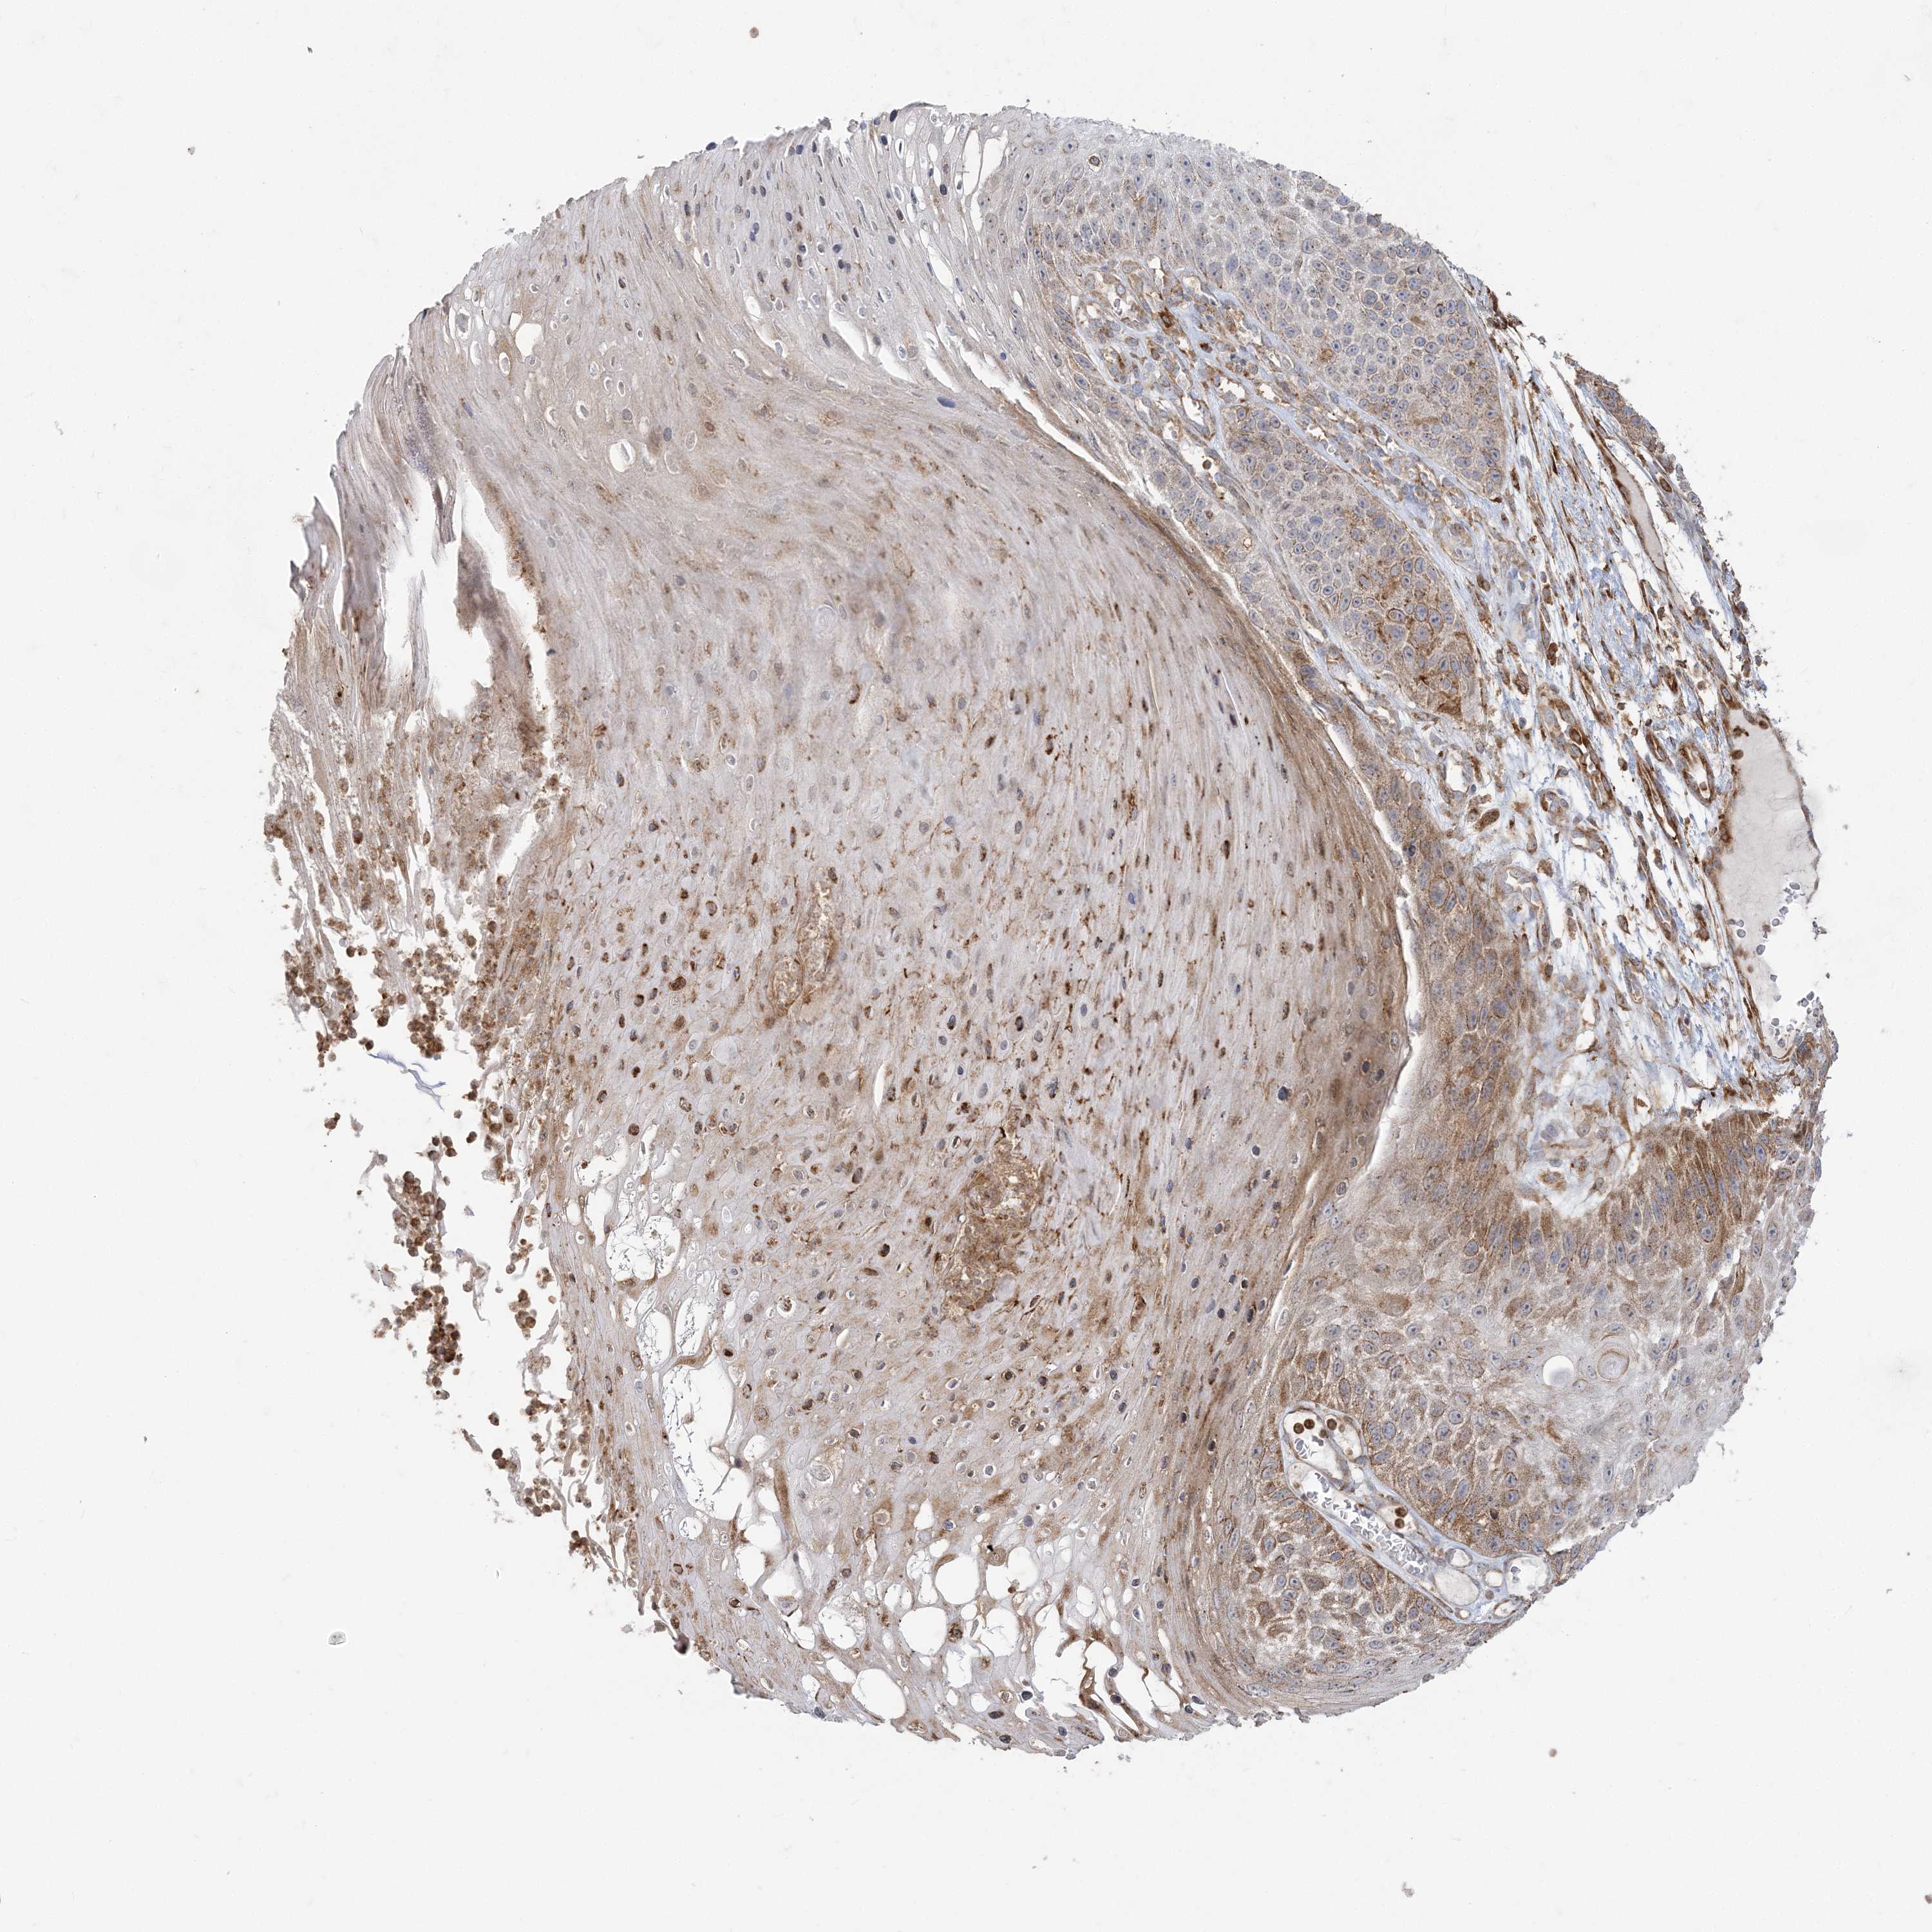

SKIN CANCER - Protein expressioni

A mouse-over function shows sample information and annotation data. Click on an image to view it in a full screen mode. Samples can be filtered based on level of antibody staining by selecting one or several of the following categories: high, medium, low and not detected. The assay and annotation is described here.

Antibody staining in the annotated cell types in the current human tissue is reported as not detected, low, medium, or high, based on conventional immunohistochemistry profiling in selected tissues. This score is based on the combination of the staining intensity and fraction of stained cells.

Each image is clickable and will lead to virtual microscopy that enables deeper exploration of all samples and also displays staining intensity scores, fraction scores and subcellular localization as well as patient and tissue information for each sample.

Antibody CAB037234

Staining

High

Intensity

Strong

Moderate

Weak

Negative

Quantity

>75%

75%-25%

<25%

None

Location

Nuclear

Cytoplasmic/membranous

Cytoplasmic/membranous,nuclear

Squamous cell carcinoma, NOS

Squamous cell carcinoma, metastatic, NOS

Basal cell carcinoma